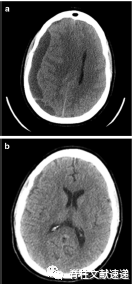

图注:40岁女性,既往多次腰椎手术史,再行翻修手术中发现发现硬膜缺损并给予修复。术后三周,病人出现进行性头痛。腰椎磁共振成像显示术区积液。再次手术探查,但未见渗漏。患者头痛持续,术后24小时进行CT扫描,显示右侧硬脑膜下血肿(SDH),中线移位。病人接受紧急颅骨切开引流减压。随访CT显示SDH恢复良好。